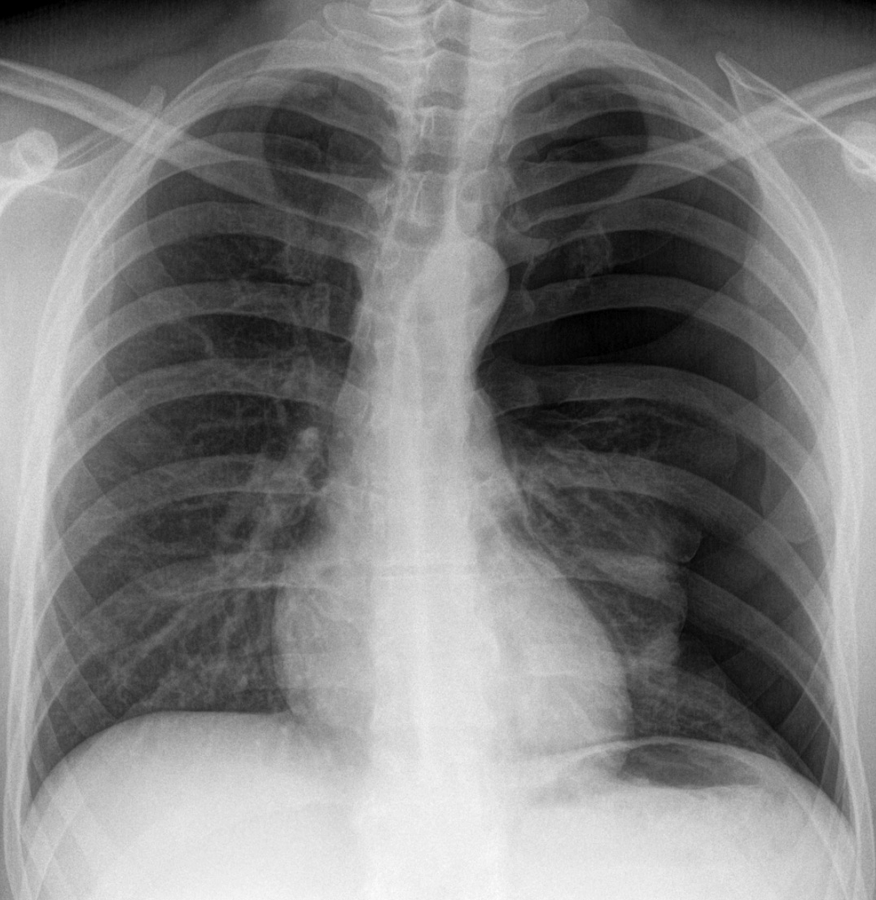

Spontanpneumothorax links (im Bild rechts). Spontanpneumothorax links (im Bild rechts). © wikimedia/Hellerhoff (CC BY-SA 3.0)